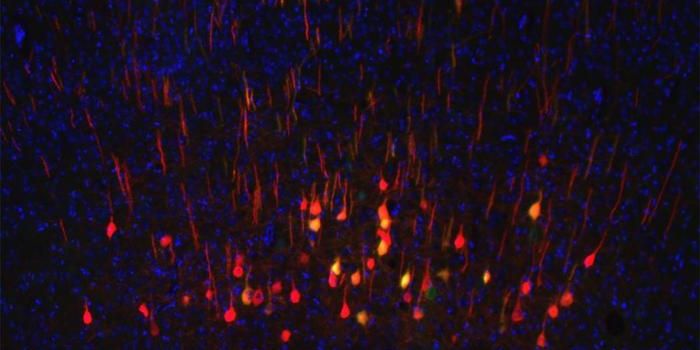

SEP 02, 2024Genetics & GenomicsWith powerful tools that sequence the genes that are being expressed in individual cells, scientists have gained new ins ...